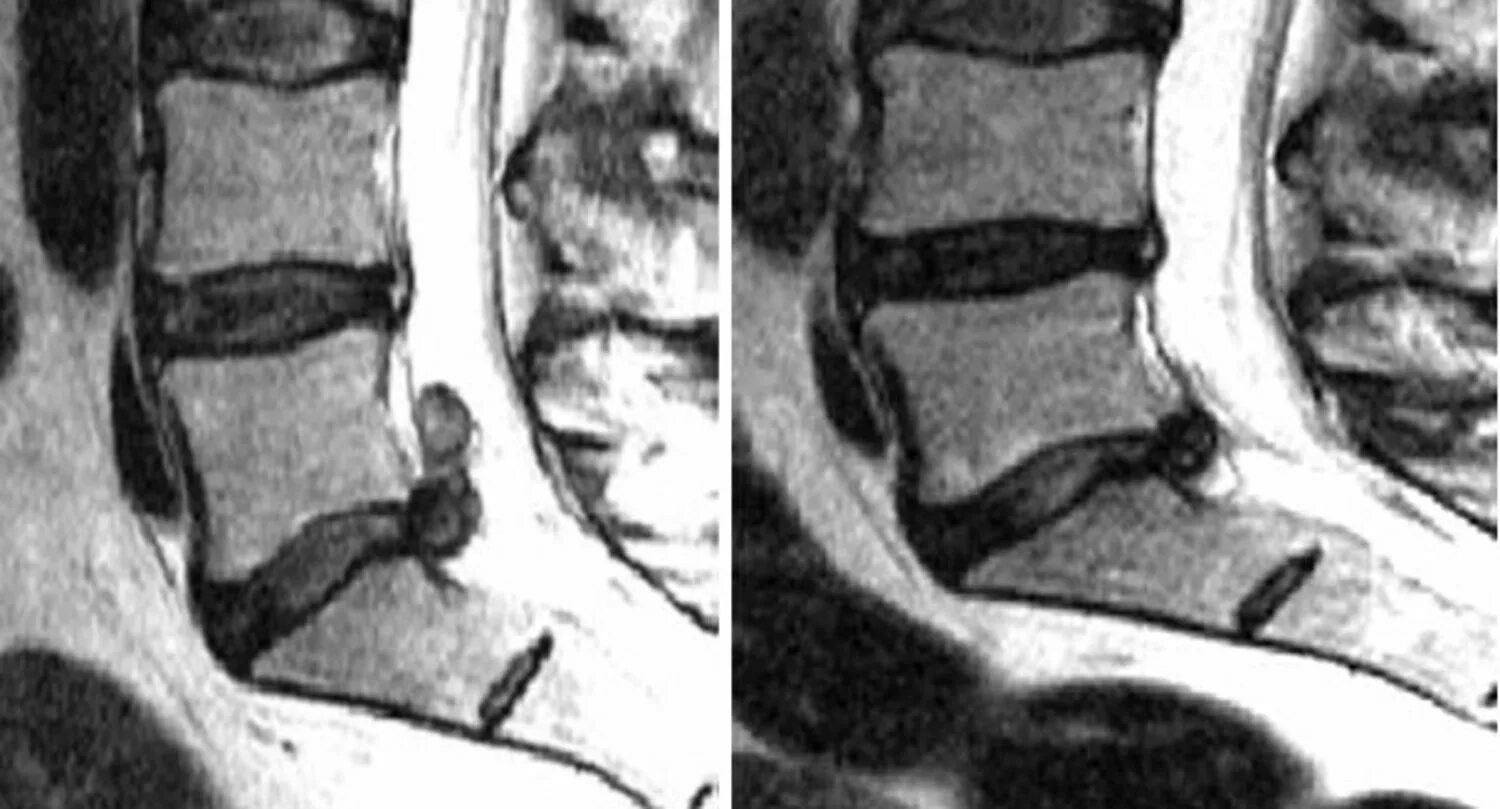

Протрузия диска l5 s1 поясничного